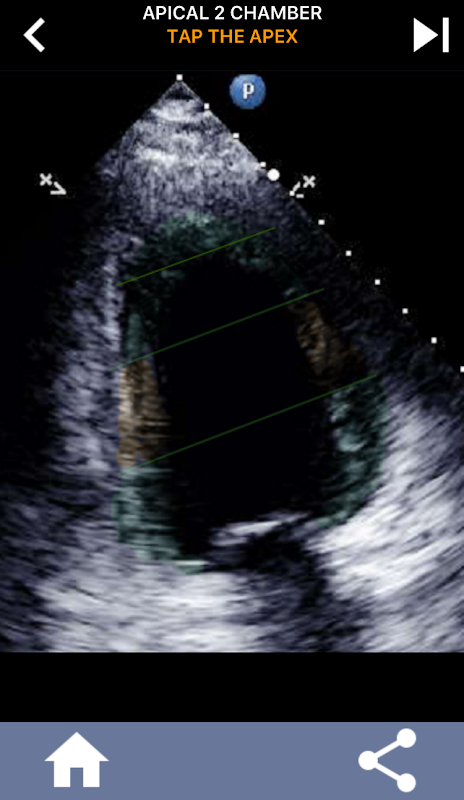

Aplikasi ini mengandungi semua pandangan gema yang menunjukkan AHA dibahagikan kepada miokardium dan akan kuiz anda untuk mengetuk segmen yang betul. Saya secara peribadi mendapati bahawa kuiz berulang-ulang berfungsi paling baik untuk saya apabila saya perlu cepat belajar / menghafal subjek. Jika anda seorang pelajar USG yang belajar echo / TTE saya fikir ini akan menjadi pelengkap yang sangat baik untuk pelajaran anda.